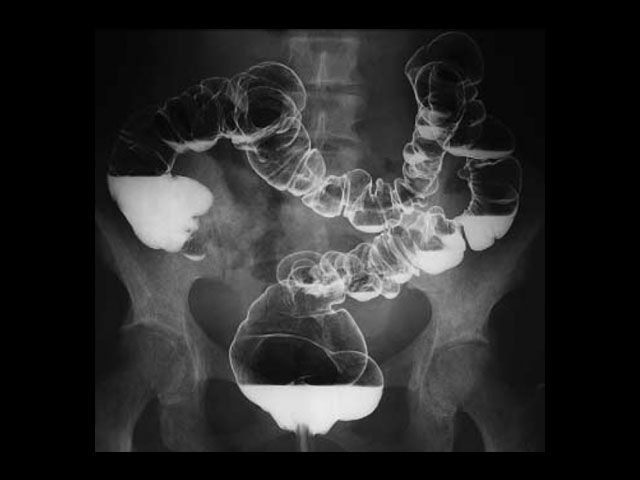

Επιπλέον ειδικές εξετάσεις όπως βαριούχο γεύμα και υποκλυσμός αλλά και ενδοφλέβια πυεολογραφία, διενεργούνται με ταχύτητα και ασφάλεια σε σύγχρονο και άνετο περιβάλλον.

Απεικόνιση 1